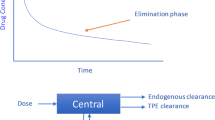

When patients receive ECMO support, important changes in drug pharmacokinetics can occur depending on interactions with the ECMO device, drug characteristics, and the patient’s clinical status [88].

The ECMO circuit itself may behave as an additional compartment by sequestering drugs, increasing volume of distribution (Vd), and changing drug clearance (CL) and elimination; moreover, the circuit may continuously release sequestered drugs even after their administration has stopped [89]. The extent of binding is influenced by drug properties such as molecular weight, plasma protein binding, degree of ionization, and lipophilicity. For instance, drugs with high lipophilicity (such as fentanyl, propofol and voriconazole) [90, 91] and/or high protein binding (such as vancomycin and ceftriaxone) [92] are more likely to be sequestered in ECMO circuits, resulting in a higher loss of the drugs [89]. Materials obviously influence the degree of drug binding, and higher drug concentrations were reported in silicone membrane oxygenators than in hollow-fiber microporous membrane oxygenators; however, there is still disagreement regarding whether the age of a circuit alters drug sequestration [91, 93].

Capillary penetration, fluid shifts and retention, pH, and plasma protein binding of drugs are all mechanisms that may lead to an increased Vd [89]. Besides, renal dysfunction, often present in ECMO patients, causes increased exposure to drugs excreted by the kidney, and continuous renal replacement therapy (CRRT) variably influences drug pharmacokinetics; however, limited data regarding the impact of the combination ECMO-CRRT on the pharmacokinetics of drugs are available [94].

Relevant variability in the pharmacodynamics and kinetics of antibiotics during ECMO has been shown in numerous studies [88, 93]; these differences may be associated with either underdosing (risk of treatment failure) or overdosing (risk of adverse events). Empirical dose adjustment is substantially impossible due to a lack of predictability. Consequently, the best approach towards personalized dosing of antibiotics is the use of therapeutic drug monitoring (TDM) [95]. Although the implementation of a TDM-based antibiotic stewardship program poses clinical, educational, and logistical challenges [96], it has been shown to be clinically beneficial and is recommended by scientific societies [97].